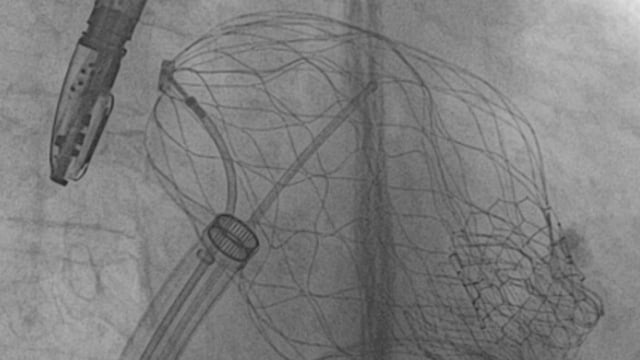

Advancing solutions for tricuspid regurgitation patients: introducing TriClip G4

19 May 2021 – From EuroPCR 2021

Watch this session presented by Francesco Maisano, Philipp Lurz, Fabien Praz, Patrizio Lancellotti  and Georg Nickenig in order to learn about patient diagnosis and selection for tricuspid transcatheter treatment with TriClip, about latest clinical data supporting TriClip therapy, and about real life experience and attest product innovation: TriClip G4.

New horizons in tricuspid therapy, the TricValve solution

Watch this session presented by Michael Haude, Christoph Naber, Mohamed Abdel-Wahab, Mohd Ghazi Azmee, Yahaya Shaiful Azmi, Katharina Kiss and Ignacio Amat Santos in order to learn about the TricValve system's approach to tricuspid regurgitation and right heart disease, to understand how this new generation of tricuspid valve system may...

TMVR today: devices, challenges, and clinical learnings

12 Sep 2025 – From PCR Rio Valves 2025

Explore the evolving landscape of transcatheter mitral valve replacement (TMVR) with a focus on innovative devices, procedural challenges, and clinical learnings. Through a series of case reports, including novel atrial fixation prostheses, devices addressing left ventricular outflow tract obstruction, and complex MitraClip interventions, this session highlights...